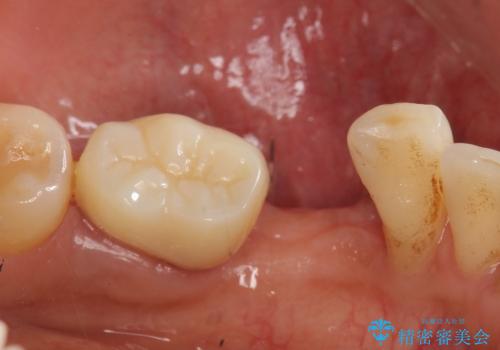

- 左下の歯並びが悪く、左側で物が咬みにくいので診て欲しいといらっしゃった方の症例です。

歯列矯正は御希望されなかったため左下4、5番目の歯を抜歯し、インプラントによる欠損補綴を行いました。

左下6も再根管治療後、オールセラミッククラウンによる補綴を行いました。